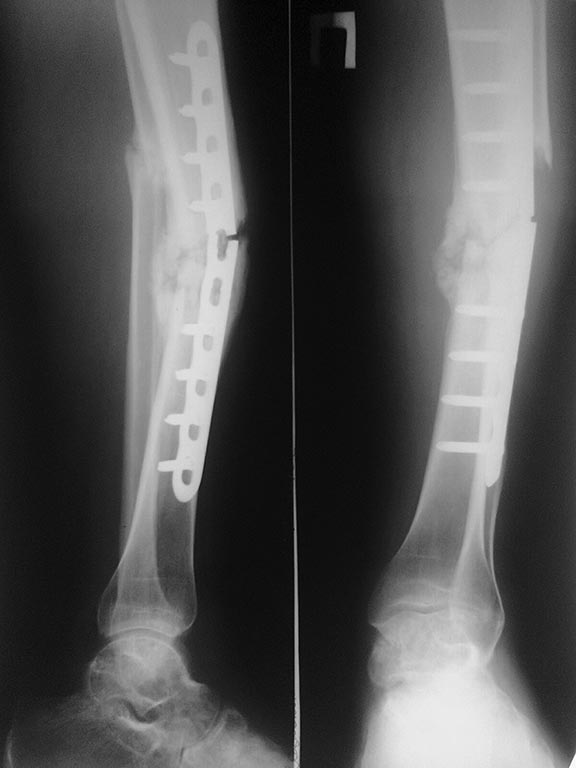

Пациент 26 лет. Травма в сентябре 2013 года в результате ДТП (сбит машиной)- закрытый перелом обеих костей правой голени. Операция в соседней ЦРБ- открытая репозиция, остеосинтез блокируемой пластиной (первичные и послеоперационные снимки утрачены). Предписанный режим не соблюдал. Обратился к нам в октябре по поводу поломки фиксатора (снимок 1). Выполнено 31.10.13: удаление металлоконструкций, БИОС неканюлированным штифтом DC с рассверливанием. П/операционный период гладкий. В январе обратился по поводу возникновения болей в месте перелома, отека, появления свища на внутренней поверхности голени. 23.01.14- ревизия свища, секвестрэктомия (множество мелких секвестров в мягких тканях вокруг мозоли). В дальнейшем рана велась при помощи VAC, зажила без осложнений. Около месяца назад вновь появились боли в области формирующейся мозоли, во втянутом рубце сформировался свищ, через который эвакуировалось несколько мелких секвестров. В настоящий момент свищ закрылся, боли несколько уменьшились. В анализах- СОЭ-16 мм/час, СРБ-28, лейкоциты крови- 6,4. Последние снимки и КТ представлены. Вопрос банален- что делать дальше? Большого опыта в лечении такой патологии не имеем. Спасибо всем откликнувшимся.P.S. За качество снимков прошу прощения (снимал на телефон).

На рентгенограммах с гвоздем иммется диастаз м/у отломками б/берцовой кости, сращения м/берцовой кости похоже так же нет. Поэтому в первую очередь необходимо выполнить динамизацию. В противном случае в скором времени можно ожидать обострения воспалительного процесса, более того Вы получите как минимум перелом блокирующмх винтов, а может и самого гвоздя.